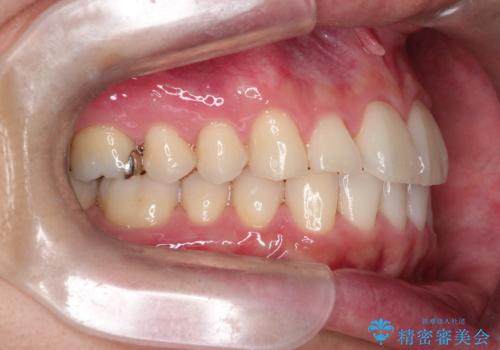

- 前歯の凸凹と顎の偏位を主訴に来院されました。

下顎の偏位を認めましたが、外科矯正を希望されなかったためできる範囲で顎の偏位を治すことができるよう治療を行なっております。

治療開始前に、下顎位の評価をおこなうことで、完成度の高い治療を行うことができました。